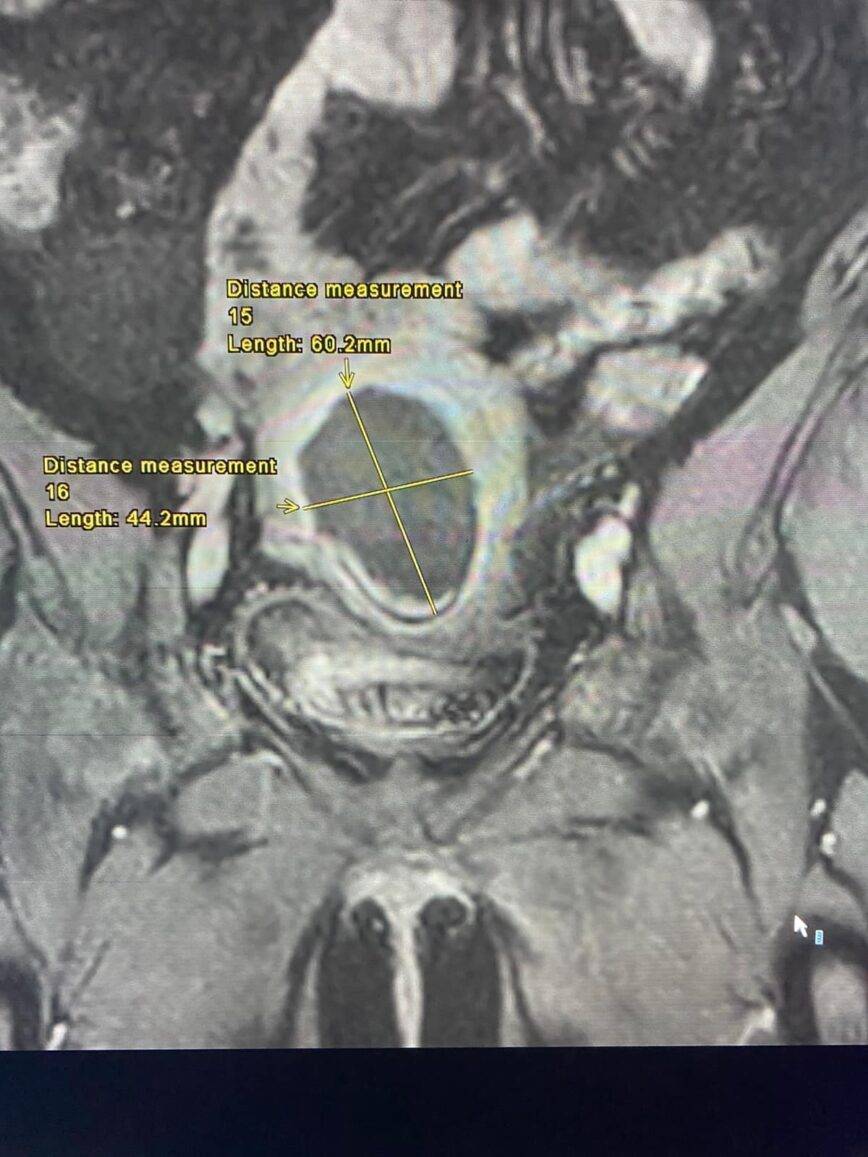

نبأ الأردن - أجرى فريق طبي متخصص من دائرة النسائية والتوليد ودائرة الأشعة برئاسة، العميد الطبيب عامر غرايبة، وأخصائي أول الأشعة تشخيصية الرائد الطبيب محمد حمدي الحياري في مدينة الحسين الطبية عملية كَي لورم ليفي رَحمي بحجم 7 سم مسبّب لنزيف رحمي مستمر وغزارة بالطمث.

وبين أخصائي أول الأشعة التشخيصية والتصوير التلفزيوني التداخلي، الرائد الطبيب محمد حمدي الحياري، أن العملية أجريت تحت التخدير الواعي و تحت توجيه جهاز التصوير التلفزيوني حيث تم إدخال مسبار الكَي داخل الورم الرحمي عبرة فتحة صغيرة في جدار البطن لا يتجاوز طولها 3 مم في وقت إجمالي بلغ 30 دقيقة دون مضاعفات وغادرت المريضة المستشفى بعد 24 ساعة من الإجراء.